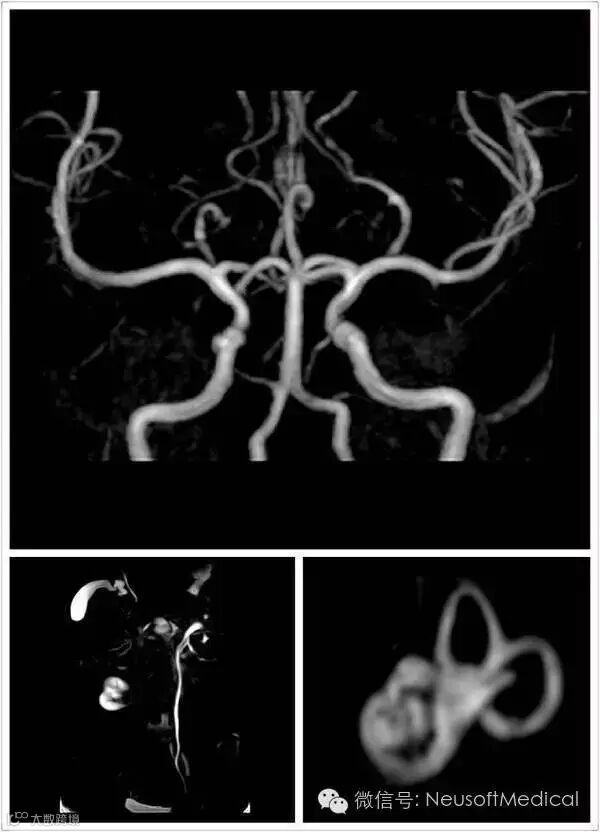

Superstar 0.35T磁共振图像质量优异,永磁之王当之无愧!